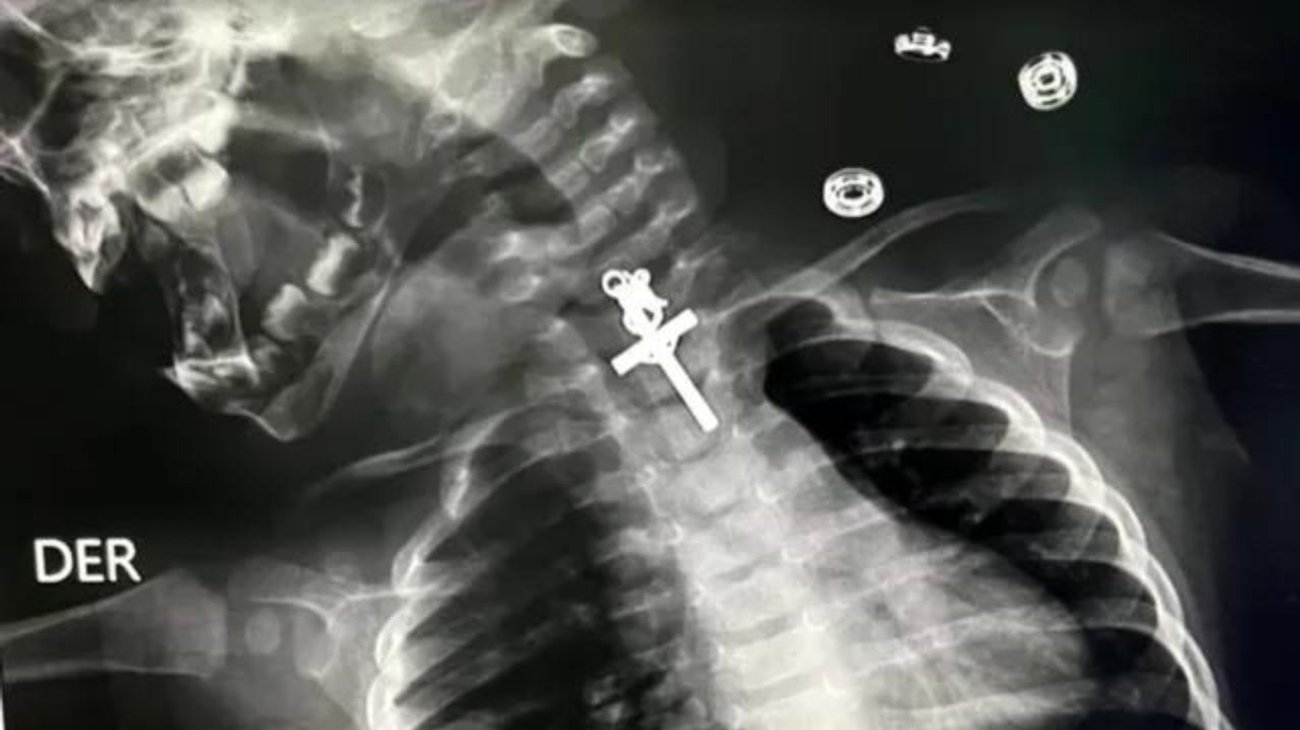

En Trujillo, Perú, una bebé de apenas 10 meses de edad fue sometida a una operación de emergencia después de ingerir un crucifijo de metal, causándole intensos dolores.

La madre, identificada como Maricarmen Sajami, llevó a su hija al hospital Víctor Lazarte, donde los médicos confirmaron la presencia del objeto en el esófago de la pequeña.

Ante la urgencia de la situación, el equipo médico realizó una cirugía de aproximadamente seis horas utilizando endoscopio y pinzas especiales para extraer el crucifijo. La madre, sorprendida por la noticia, atribuyó el incidente a un descuido común y a la naturaleza curiosa de los niños.

La intervención quirúrgica fue llevada a cabo por anestesiólogos y gastroenterólogos, quienes lograron extraer con éxito el objeto extraño. Después de la operación, la madre compartió una conmovedora imagen en la que sostenía en la palma de su mano el crucifijo que había sido retirado del cuerpo de su hija.